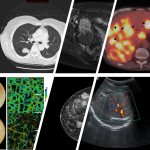

In today’s fast-evolving medical landscape, the role of advanced medical imaging has become super important in supporting every stage of cancer care. The ability to see inside the body, from the early detection of cancer to monitoring treatment outcomes, has changed the way physicians work and how patients experience their journey. Medical imaging now spans a range of techniques, from digital breast imaging to nuclear medicine scans—all designed to offer precise, detailed insights while helping patients and care teams steer through the often overwhelming treatment process.

This opinion piece explores various radiology techniques, highlighting their benefits, how they have evolved, and what patients can expect from them. We’ll take a closer look at digital breast imaging, computed tomography, interventional radiology, and more. Each imaging modality offers a unique perspective into the fine points of cancer care and treatment—a factor that is both critical and must-have for ensuring the right interventions at the right time.

Nuclear medicine is one of those areas where imaging does more than simply map out the body’s blocks and tissues. Instead, nuclear medicine scans like PET/CT and PET/MRI focus on both structure and function. By administering a small amount of a radioactive substance—known as a radiotracer—physicians can track how cancer cells absorb the tracer differently from normal cells. This process provides a dual-layer insight: not just showing the physical layout of organs, but also the functional performance of tissues.

A PET/CT scan is particularly noteworthy due to its combined approach. The CT component of the scan provides the detailed structural image, while the PET portion reveals metabolic activity within the tissues. This merged view enables a more comprehensive understanding of cancer behavior. In some cases, SPECT/CT scans are used, especially in scenarios where patients are receiving molecular therapies such as targeted drug delivery that employs radiation directly to the tumor.

The evolving landscape of radiology is continually proving to be a cornerstone in modern cancer care. From digital breast imaging and CT scans to interventional procedures and nuclear medicine, these advanced techniques offer patients and care teams the tools needed to get around the confusing bits and tangled issues of cancer diagnosis and treatment. By providing detailed images and functional insights, radiology helps untangle the complexities that have traditionally made cancer care a nerve-racking experience.